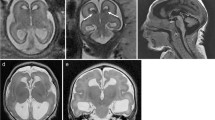

To describe the morphological stages of insular sulci and gyri development we carried out a macroscopical study on 21 human fetal brains, showing no anomalies, from 13 to 28 gestational weeks (GWs). Particular focus was given to morphological appearance during the development of insular and periinsular structures, especially the gyration and sulcation of the insula, central cerebral region and opercula, as well as the vascularization of these regions. The periinsular sulci and the central (insular and cerebral) sulci were the first macroscopical structures identified on the lateral surface of the human fetal cerebral hemisphere with earlier development on the right hemisphere. Here we describe five stages of insular gyral and sulcal development closely related to gestational age: stage 1: appearance of the first sulcus at 13-17 GWs, stage 2: development of the periinsular sulci at 18–19 GWs, stage 3: central sulci and opercularization of the insula at 20–22 GWs, stage 4: covering of the posterior insula at 24–26 GWs, stage 5: closure of the sylvian fissure at 27–28 GWs. We provide evidence that cortical maturation (sulcation and gyration) and vascularization of the lateral surface of the brain starts with the insular region, suggesting that this region is a central area of cortical development.